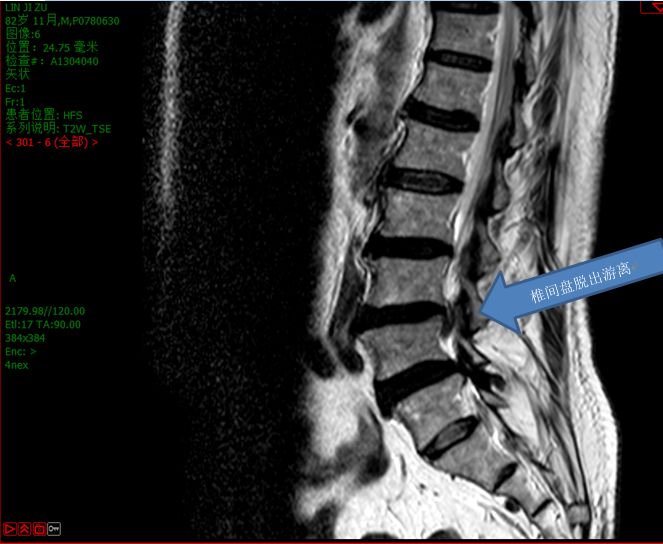

很快,腰椎核磁共振结果出来了:腰3/4椎间盘明显脱出。远端下垂至腰4椎弓根下方。

腰椎间盘突出根据突出物的形态特点,可分为:膨出、突出、脱出、游离等。而其中脱出、游离是最严重的,如果不能及时治疗,受压迫的神经、脊髓坏死,可出现大小便*禁失**、下肢无力等不可逆的神经损伤。因此,建议患者在出现症状以后一定要及时到医院明确诊断。

对于不合并有腰椎不稳或滑脱的腰椎间盘突出症,可以首先考虑微创脊柱内镜治疗。虽然有一定的复发率和残留率,但发生的概率还是比较低的。对于椎间盘脱出、游离的腰椎间盘突出症,也可以选择微创脊柱内镜手术,虽然手术难度大一点、操作复杂一点,但还是可以给自己一次微创的机会,毕竟开放融合手术是终极治疗方案,而且微创脊柱内镜手术并不影响以后行开放融合手术。